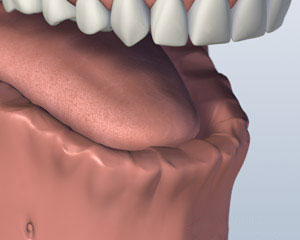

• Step 1: If you have lost all of your teeth in one or both jaws and require a removable prosthesis that remains in place more firmly than a conventional removable prosthesis, the overdenture connected to two or more implants is the answer when the prerequisites are met.

• Step 2: An overdenture involves installing two or more dental implants that will be used as a secure foundation to attach the prosthesis.

• Step 3: For the overdenture, either ball abutments or a small bar between the abutments are used. The prosthesis is fitted with corresponding devices underneath.

• Step 4: The overdenture is now in place. It looks and functions like normal teeth. You can now eat whatever you like and laugh without having to worry about the prosthesis falling out.